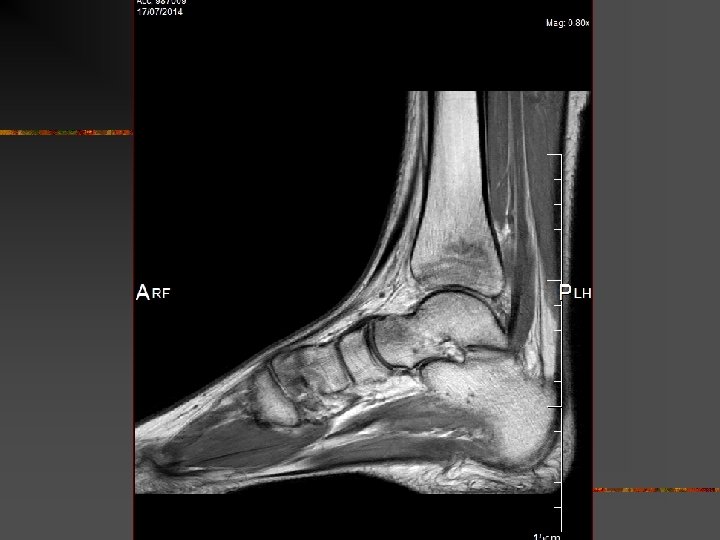

SCP : Rappel anatomique Les acteurs du conflit: Le tendon du m. long fléchisseur de l’hallux

SCP microtraumatique : Lésions n n n Inflammation récessus capsulo-ligamentaires postérieurs Arthrose talo-crurale ou sous-talienne postérieure # de stress tibio-talienne postérieure Lésion ostéo-chondrale dôme talien postérieur Tendinopathie Fléchisseur Propre de l’Hallux (TS > fissures IT)

SCP : Diagnostics différentiels Avec flexion plantaire douloureuse - Tendinopathies du Long Fléchisseur de l’Hallux . Situation : gouttière du processus post. Du talus ( tunnel ostéo-fibreux non extensible) . Facteur favorisant : jonction MT basse - jonction N = niv. Art. tibio-talienne - jonction basse = niv. Talus ou face médiale calca. n (néanmoins anomalies le plus svt asymptomatiques) - Lésion ostéochondrale dôme talus ou du pilon tibial (séq. T , kyste , …)